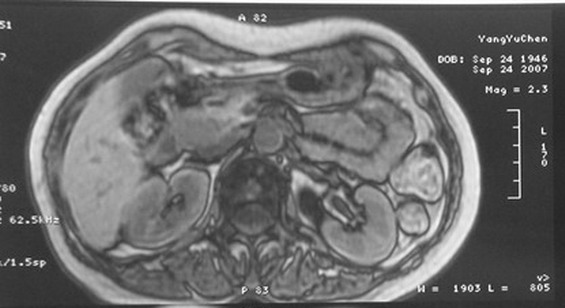

标题: MRI2066:腹膜后占位,请会诊,CT18531近期扫描图像

无明显不适,体检发现,

mri基本排除血管类肿瘤,明显强化说明极富血供,临床无症状,考虑胰岛细胞瘤可能大。

像是胆总管囊肿,但要警惕胰头病变。

强化明显,并见有血管与之相连;考虑巨淋巴增生症.